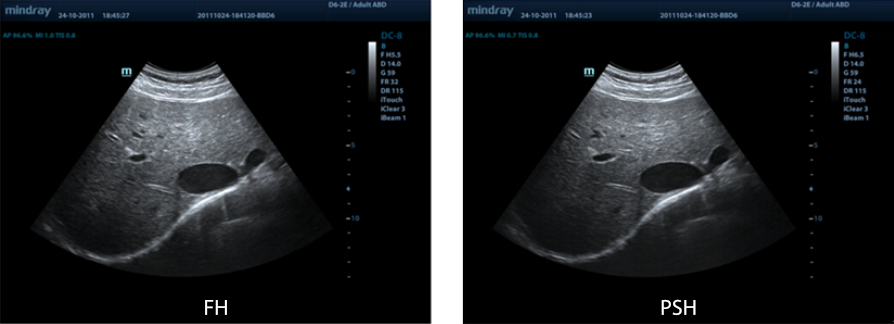

PSHI? (Phase Shift Harmonic Imaging)

Purified Harmonic Imaging (Pencitraan Harmonis yang Dimurnikan) agar resolusi kontras lebih baik, memberikan gambar yang lebih jelas dengan resolusi luar biasa dan minim derau.